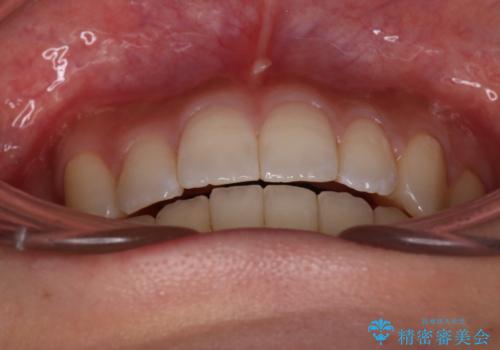

正中もズレることなく主訴である八重歯と叢生を改善することができました。

患者様の満足度も高く治療を終えられました。